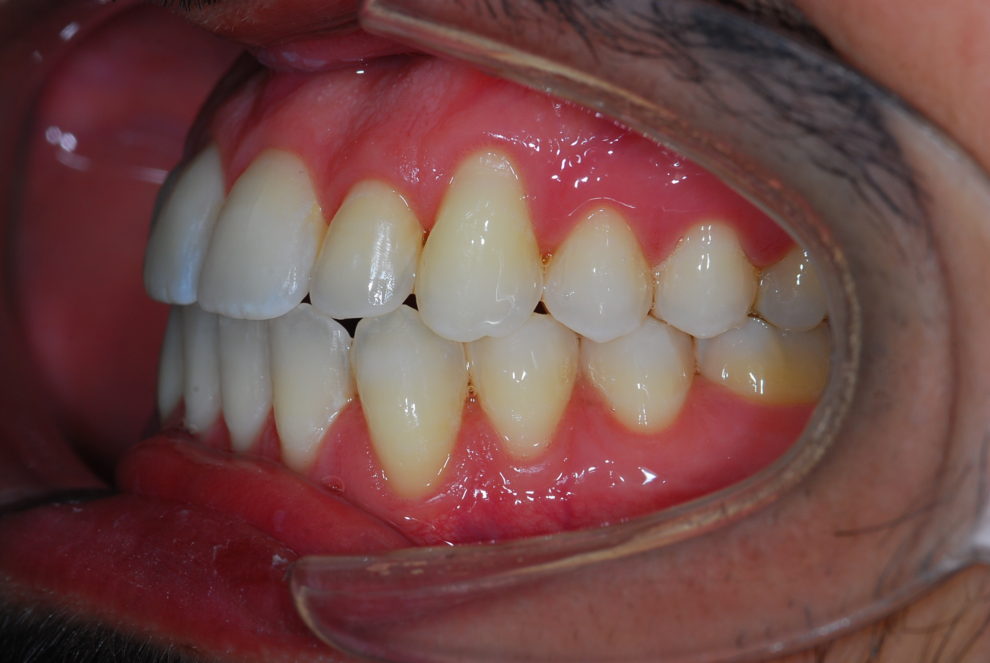

Ortodoncia + Mordida abierta

Nuestro paciente Manuel Vergara Gil acudió a nuestra clínica, y se le hizo una Ortodoncia.